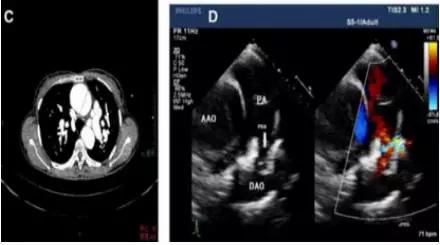

②主动脉夹层在二维超声上表现为病变部位主动脉增宽,其内可见丝裂的内膜反射,该内膜将增宽的主动脉分为真假两腔。

③有时可显示真假两腔相交通之处,表现为撕裂的内膜上有回声中断。假腔中常可显示云雾状回声反射和附壁血栓

在二维超声中可见主动内分离的内膜片呈内膜摆动征,主动脉夹层分离形成主动脉真假双腔征。有时可见心包或胸腔积液。

应用食管超声心动图。结合实时彩色血流显像技术观察升主动脉夹层分离病变较可靠。对降主动脉夹层也有较高的特异性及敏感性。